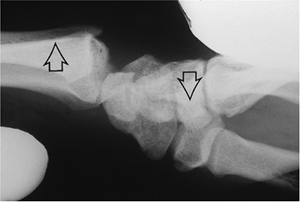

![]() |

Figure 11.2-6 DISI deformity as seen in an established scapholunate dissociation. A. AP view of the wrist showing a widened scapholunate space (vertical arrows). B. Note the dorsally rotated lunate (arrows) on the lateral view.

|